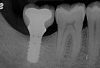

Clinical exposure of a circumferential lesion that demonstrates 3 mm of bone loss. No cement was present, suggesting that the lesion was of bacterial origin. Surface decontamination included citric acid.

Figure 2